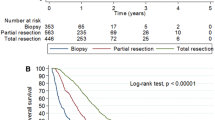

Descriptive statistics are presented in Table 1. Tumor resection was performed in 176 patients (82%). The majority of patients were functionally independent with KPS ≥ 70 prior to surgery (n = 150, 70%) and received adjuvant radiochemotherapy (n = 165, 77%). Median survival in the entire population was 374 days.